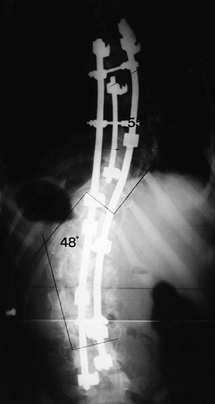

Figure 159.5. Postoperative radiograph of patient in Figure 159.3,

treated with Cotrel-Dubousset segmental instrumentation. This

triple-rod technique distributes corrective forces over many spinal

segments using multiple fixation hooks. Combined with anterior thoracic

and lumbar releases, this approach provided 45% correction of the

thoracic curve (101° to 55°) and 55% correction of the lumbar curve

(108° to 48°).